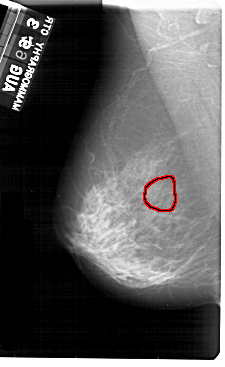

A_1954_1.LEFT_CC

LEFT_CC LINES 5491 PIXELS_PER_LINE 3256 BITS_PER_PIXEL 12 RESOLUTION 43.5 OVERLAY

FILE: A_1954_1.LEFT_CC.OVERLAY

TOTAL_ABNORMALITIES 1

ABNORMALITY 1

LESION_TYPE CALCIFICATION TYPE PUNCTATE DISTRIBUTION CLUSTERED

ASSESSMENT 4

SUBTLETY 3

PATHOLOGY BENIGN

TOTAL_OUTLINES 1

BOUNDARY